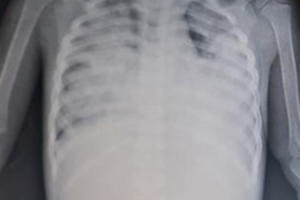

Vừa qua Bệnh viện Nhi Đồng Thành Phố tiếp nhận một trường hợp trẻ sơ sinh CB. N. L. T. V. 29 ngày tuổi, nữ, ngụ ở Tiền Giang. Khai thác bệnh sử ghi nhận trẻ...